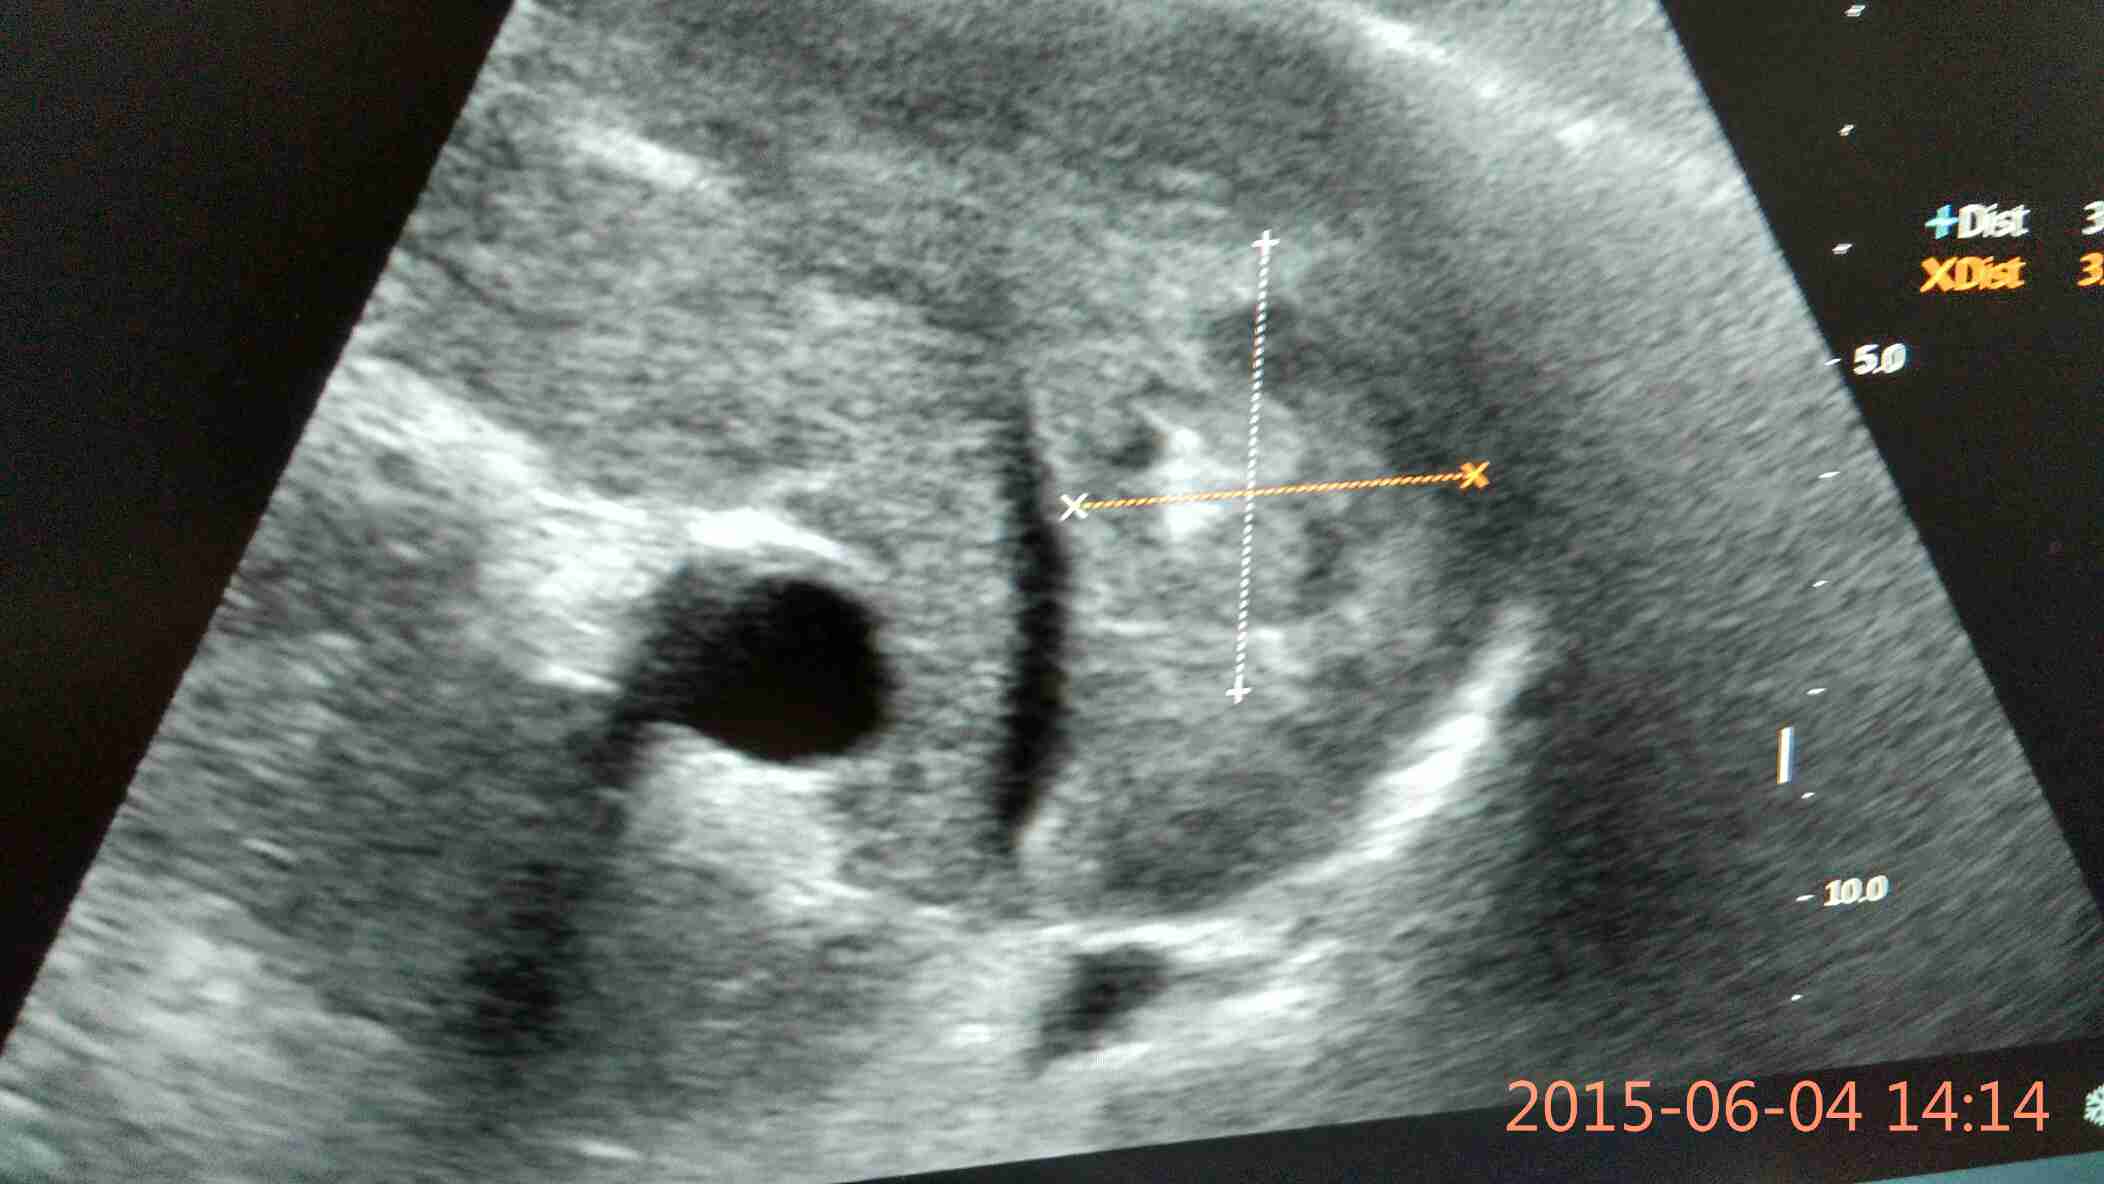

肝硬化 ( hepatic sclerosis;cirrhosis of liver )